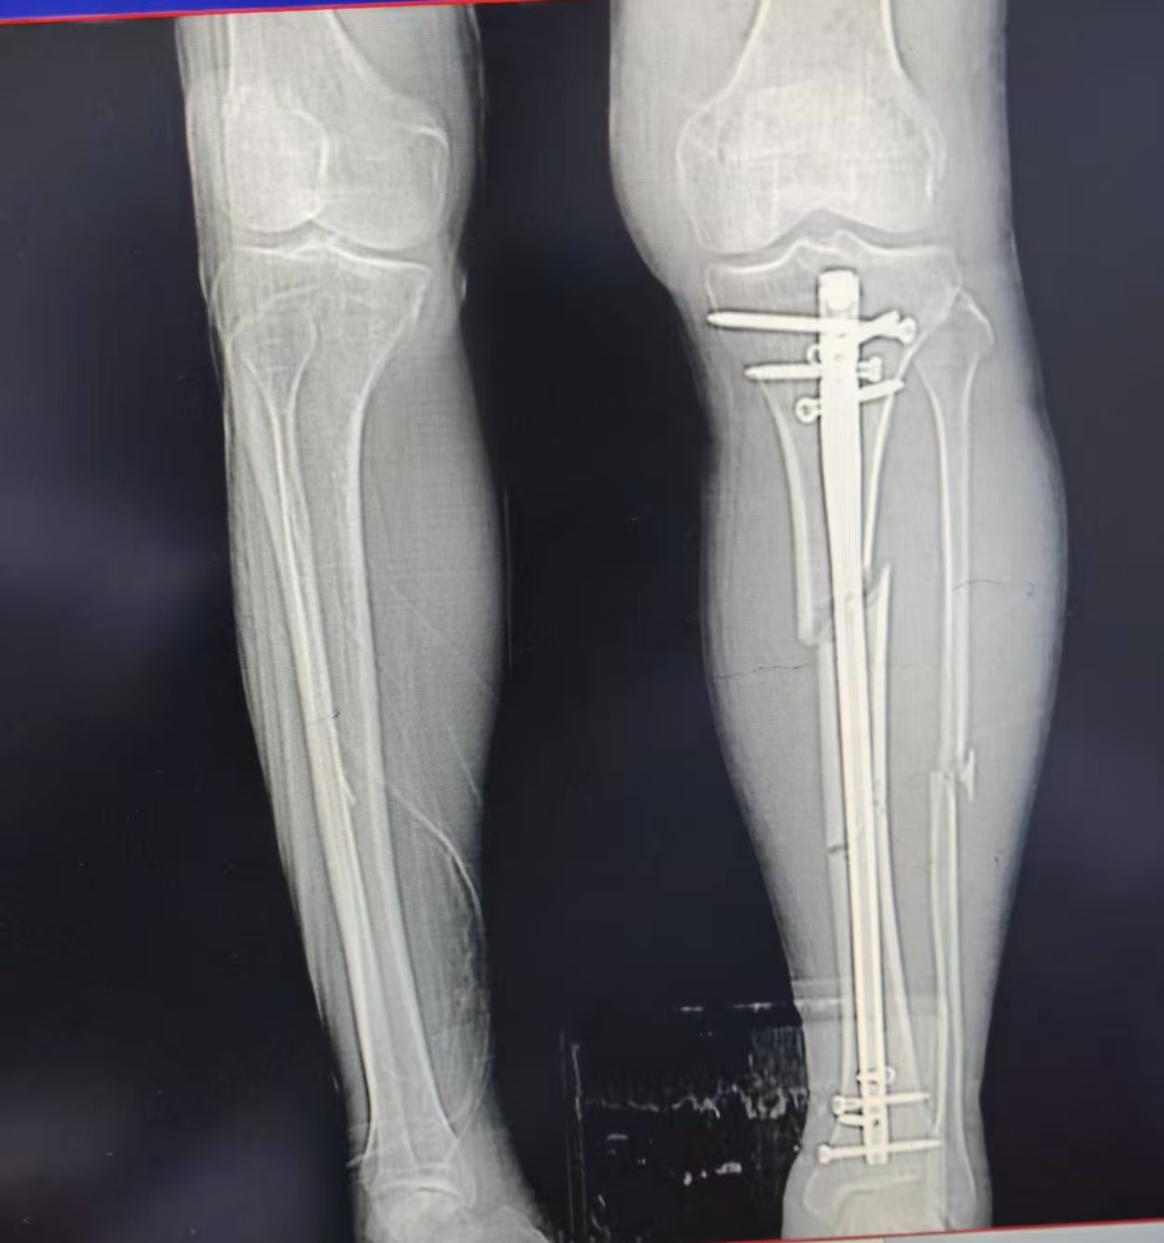

在充分的术前准备与精准的术中操作下,黄其裕副主任医师团队成功为李叔实施了闭合复位髓内钉固定术。术后复查X光片显示,原本呈“三节棍”状错位的胫骨已实现解剖对位,髓内钉位置理想,内固定坚强可靠。李叔的左小腿上,仅留下几处微小的缝合口。

术后影像